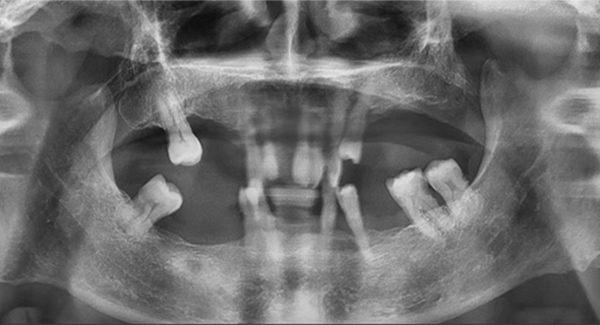

這個病例有一個特點,牙齒還在,但沒有功能。從表面看牙冠是完整的,但“金玉其外”,內部已經空了,牙根也爛穿了,無法咀嚼也失去了修復的條件,沒有保留價值。

全口病例:咬合重建,磨刀不誤砍柴功

另一個全口種植案例,除了缺牙、骨量等常見問題外,他的咬合還是內傾的深覆合,這是最大的治療難點。也就是說,患者的咬合不正常,如果按常規的思路種植后直接戴臨時牙冠,當他半年后戴上最終牙冠時,整個咬合可能不會理想,到那個階段再去調整咬合,效果可能不太好,人也比較受罪。

這位患者不到60歲,但由于后牙全部缺失多年,殘留的前牙已松動且上下無法接觸,他基本沒辦法正常咀嚼,人非常消瘦。完成治療后我跟蹤了這個病例一年,從前后對比照片可以看出,能正常吃東西后他的臉上漸漸也有肉了。